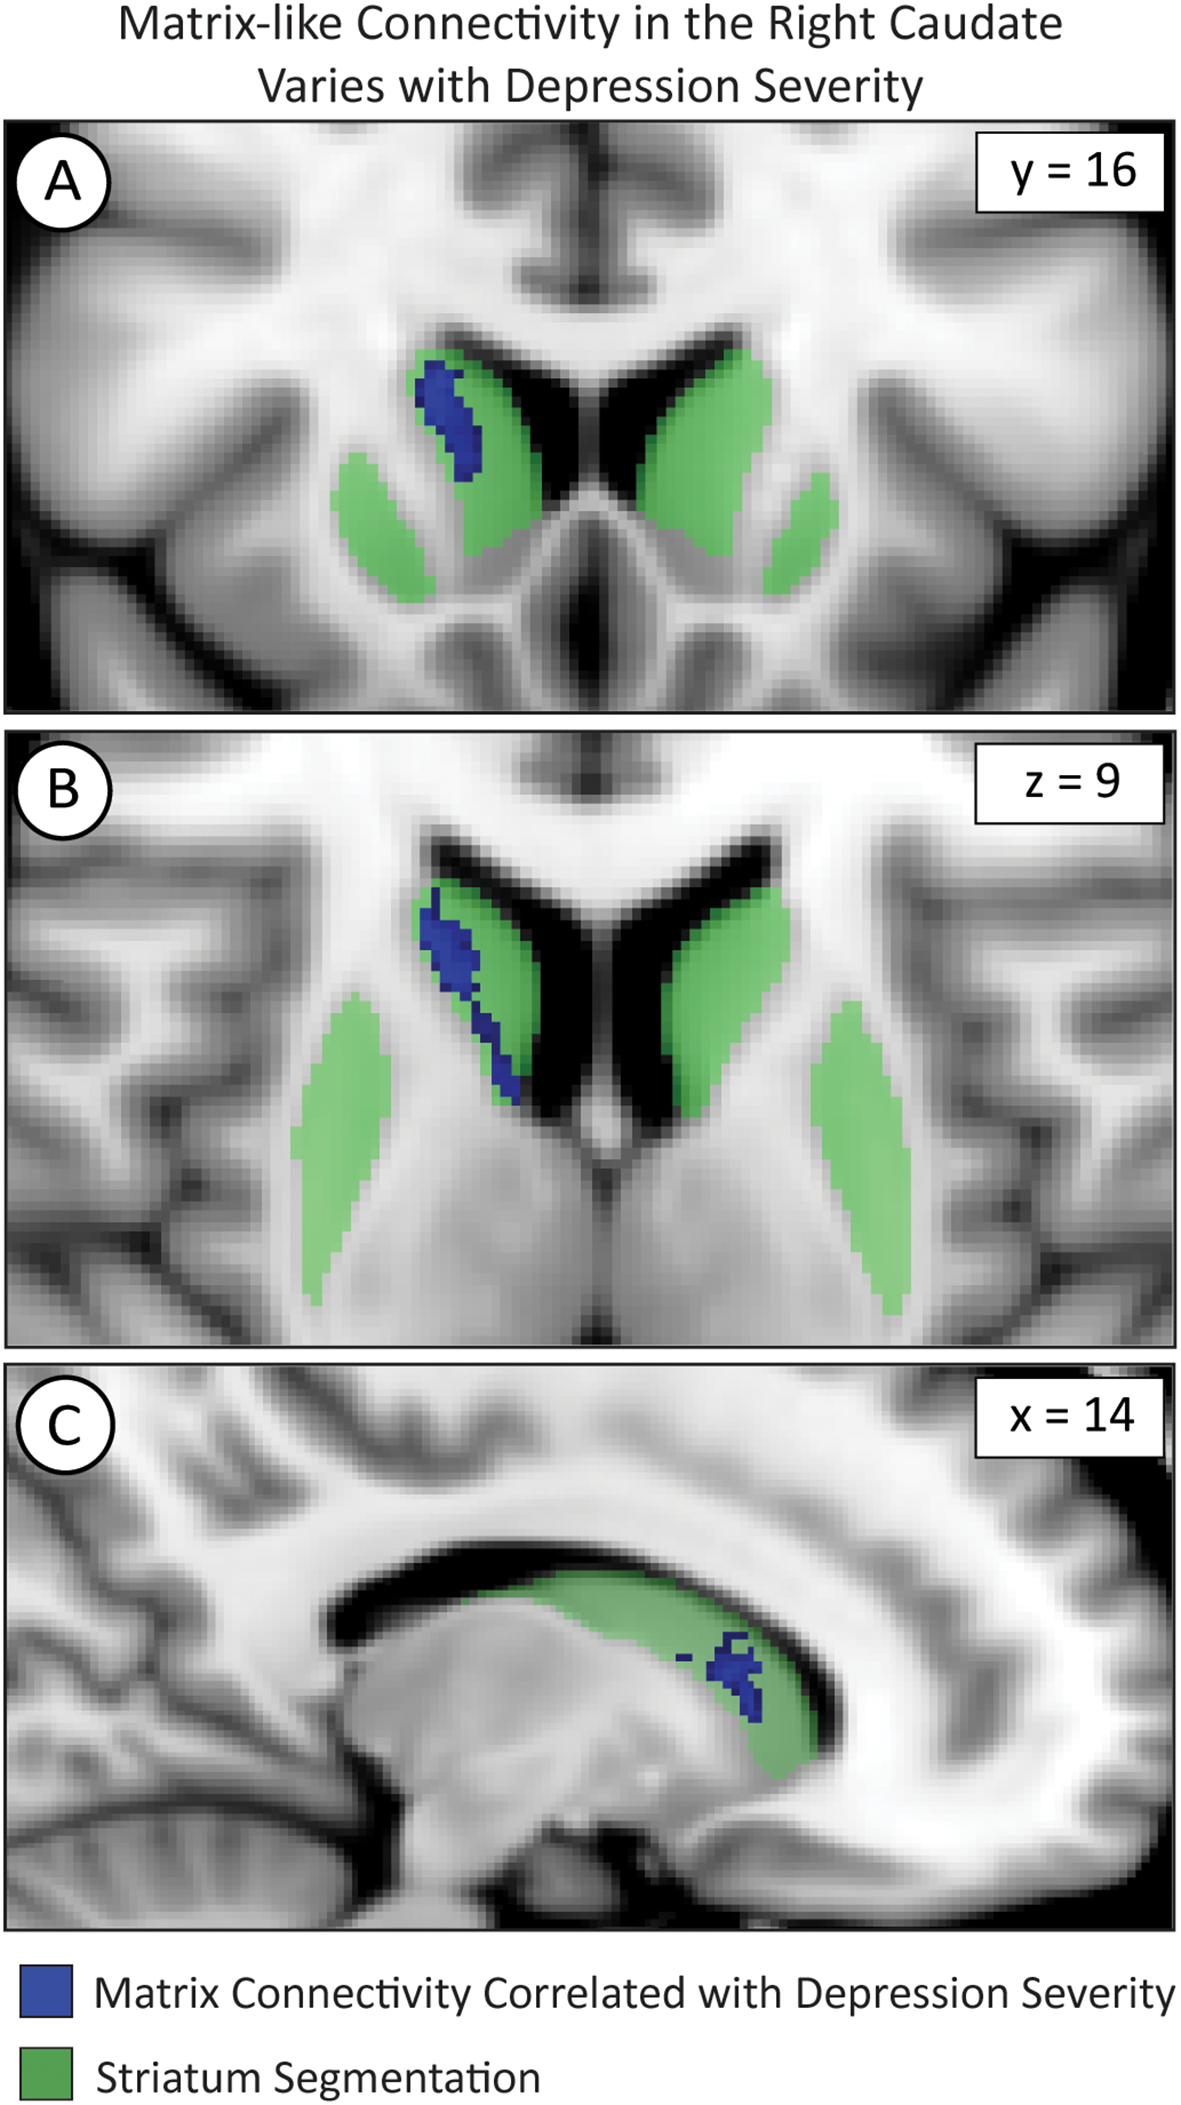

3.8 Compartment biases correlate with MDD severity

We used FSL randomise to test if compartment-like connectivity varied with depression severity (Figure 4). We identified a region in the right caudate where matrix-like bias was significantly correlated with depression severity (higher matrix-like volume in subjects with higher standardized depression scores). Both matrix-like (F1,531, p = 0.043) and striosome-like (F1,531, p = 4.9x10-4) volumes in the caudate were significantly correlated with MDD severity. Compartment-like volume in the putamen (Figures 2, 3) did not correlate with MDD severity. We performed a post-hoc analysis, extracting compartment-like volumes in the caudate for each of our severity subgroups to identify the drivers of this group-level effect (Figure 5).

Figure 4

Voxelwise testing with FSL’s randomise identified voxel clusters whose matrix-like connectivity correlated with depression severity in the caudate as shown in the coronal (A), axial (B), and sagittal (C) planes. The images adhere to radiographic convention and coordinates follow MNI convention.

We compared eTIV-normalized compartment-like volumes in the whole-caudate between a combined mild/moderate severity group and a combined severe/very severe group. In the caudate, the severe/very severe group showed a 26% increase in matrix-like volume (p = 1.2x10-3) and a 29% decrease in striosome-like volume (p = 1.1x10-3) relative to the mild/moderate group. Raw compartment-like volume measures also exhibited this difference: Matrix (Mild/Moderate: 1936 mm3 vs. Severe/Very Severe: 2338 mm3; p = 1.4x10-3); Striosome (Mild/Moderate: 894 mm3 vs. Severe/Very Severe: 611 mm3; p = 8.0x10-5).